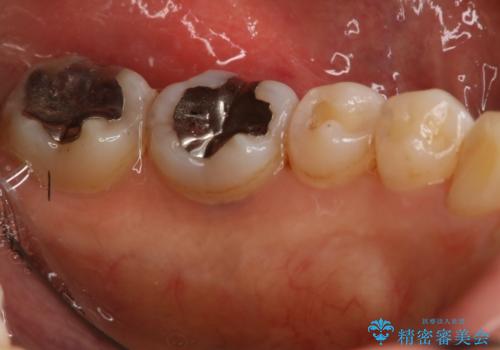

下の奥歯の銀歯を白くしたい

- 左下奥歯のメタルインレーを白くしたいと希望された患者様です。

形態、切削量などを考慮し、セラミックインレーにて治療を行いました。

メタルインレー、う蝕除去後にCRにて裏層した上で、形成・印象を行いました。